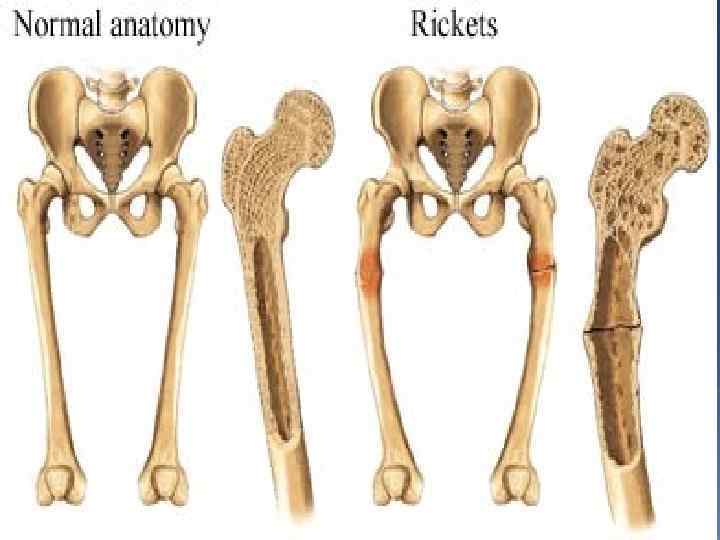

LIPID SOLUBLE vitamins It is found in cheese, milk, liver, green vegetables. It`s deficiency may cause night blindness. It is found fish, butter, milk, cheese and egg. It`s deficiency may cause rickets.